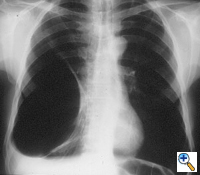

| Figure 3: Chest x-ray of a large bulla with true infection; after the appropriate medical treatment fever, hemptysis and fluid level persisted and the bulla was resected. |

Surgery is generally indicated to modify the functional status of the underlying lung by (1) relieving restrictive changes; (2) increasing compliance and airway caliber; (3) improving V/Q ratio; and (4) decreasing the physiologic dead space. These goals are easy to obtain in patients with enlarging bullae and minimal underlying lung disease. These are the best candidates for surgery and optimal results can be expected. Surgery is also indicated to treat complications related to the bullae, such as pneumothorax, true infection (Figure 3), hemoptysis, cancer (Figures 4, 5), and pain.